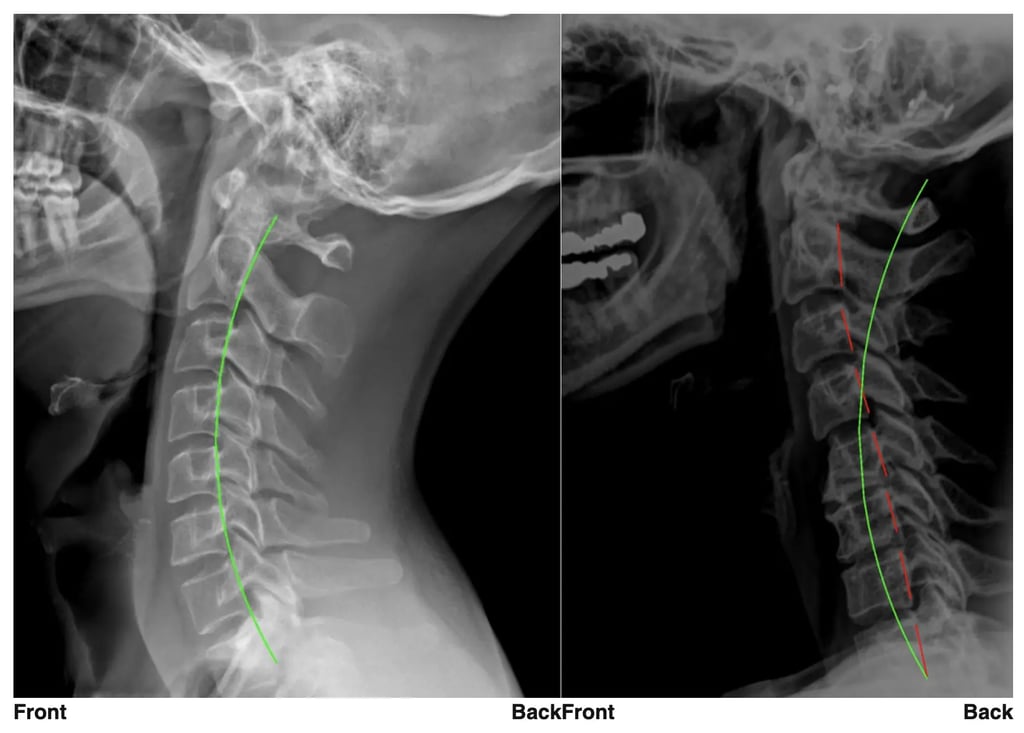

Precise X-Ray Reports

We use state-of-the-art technology from PostureRay to visualize your digital x-rays to measure spinal alignment and determine exactly what type of care is right for you.